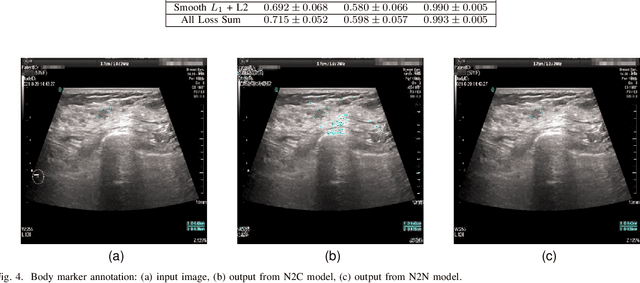

Abstract:Accurately annotated ultrasonic images are vital components of a high-quality medical report. Hospitals often have strict guidelines on the types of annotations that should appear on imaging results. However, manually inspecting these images can be a cumbersome task. While a neural network could potentially automate the process, training such a model typically requires a dataset of paired input and target images, which in turn involves significant human labour. This study introduces an automated approach for detecting annotations in images. This is achieved by treating the annotations as noise, creating a self-supervised pretext task and using a model trained under the Noise2Noise scheme to restore the image to a clean state. We tested a variety of model structures on the denoising task against different types of annotation, including body marker annotation, radial line annotation, etc. Our results demonstrate that most models trained under the Noise2Noise scheme outperformed their counterparts trained with noisy-clean data pairs. The costumed U-Net yielded the most optimal outcome on the body marker annotation dataset, with high scores on segmentation precision and reconstruction similarity. We released our code at https://github.com/GrandArth/UltrasonicImage-N2N-Approach.